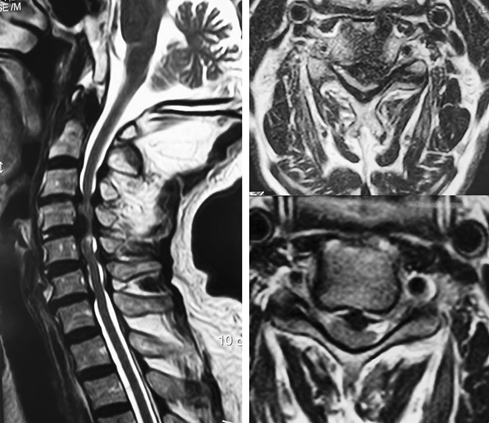

经过多方打听,张大爷慕名来到漯河市中心医院,找到脊柱外科副主任李玉伟教授。经过进一步细致的检查,李玉伟教授告诉张大爷他患的是比较麻烦的“颈腰综合征”,其中颈椎病最重,颈椎病中4个节段都存在病变,尤其颈3-4、颈4-5是椎间盘巨大脱出,严重压迫了张大爷的颈部脊髓,是本次瘫痪的“元凶”,需要手术治疗。

“巨大突出椎间盘”

老人有着非常强烈的想摆脱轮椅的愿望,为取得更好的手术效果,李玉伟教授带领科室副主任医师周鹏、崔巍等多名技术骨干仔细研究病情后,决定依靠3D打印技术,应用3D打印椎间融合器,为张大爷实施微创的颈椎前路椎间盘切除融合内固定术,使手术创伤最小化,风险最低化。

“3D打印椎间融合器”